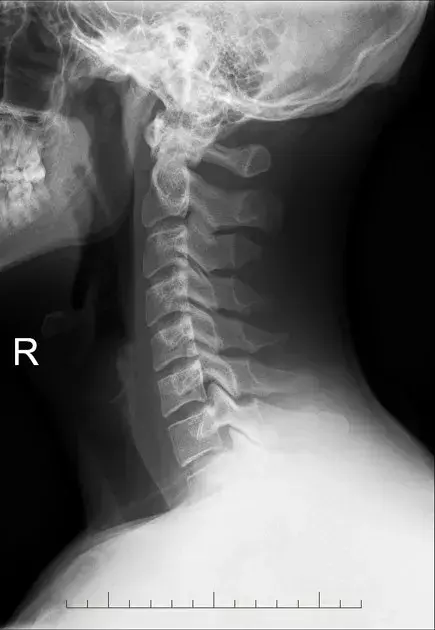

图2、正常的颈椎侧位片

图 6、颈椎生理曲度变直

图9、颈椎侧位片,正常的椎体后缘是对齐的。

图11:颈椎侧位。正常的颈椎对准。在C3-C4,C4-C5和C5-C6水平上注意到小的前部骨赘形成。C4-C5水平的椎间隙变窄,轻度终板硬化。还注意到C4-C5和C5-C6水平的关节肥大。